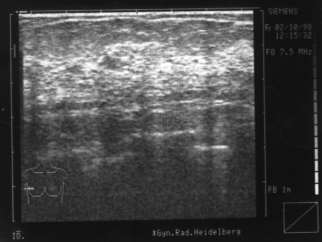

Nachher:

Innerhalb von 2 Tagen wächst dieser große Knoten in der linken Brust der Klientin. Der Prof. will die Brust abnehmen. Die Klientin aber nutzt die kurze Zeit bis zum OP-Termin zur Selbstheilung und läßt sich von Brigitte mit 6 Synergetik Therapie Sitzungen helfen, den Hintergrund selbst aufzulösen. Dazu mußte es einen konkreten Auslöser mit dem Thema „Kind“ geben, der so schnell arbeitete und den Knoten produzierte. Dieser war leicht zu finden und der wirkende Kontext in der Innenwelt wurde verändert. Der Prof. staunte nicht schlecht, als er den Knoten per Ultraschallbild nicht mehr finden konnte. ... Er interessierte sich für die Synergetik Therapie und lädt Brigitte Schiechel zur Zusammenarbeit ein.